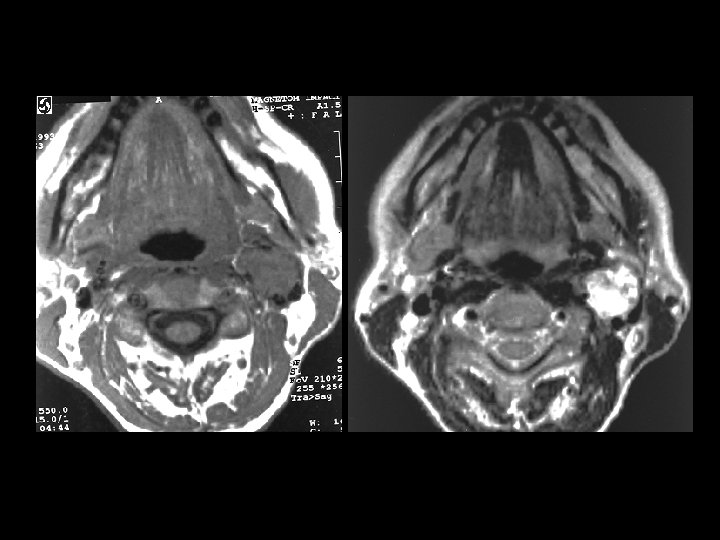

Carotid body paraganglioma • • Findings: – Intensely enhancing mass in the carotid sheath that splays the internal and external carotid arteries ddx: – Glomus vagali – Carotid aneurysm